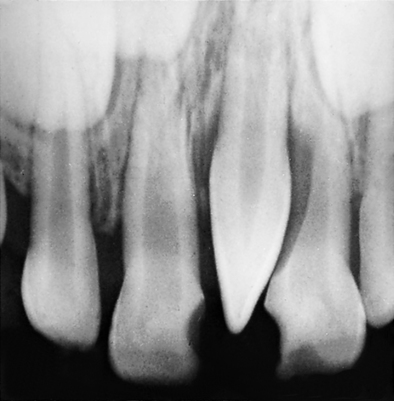

Supernumerary teeth arising in the midline of the maxillae are termed mesiodens (Fig. 7-5) and are the most common supernumeraries. The maxillary distomolars are the next most common supernumerary teeth. These distomolars are also called fourth molars and are located distal to the maxillary third molars. Mandibular distomolars do occur but not nearly as often as in the maxilla. A supernumerary tooth situated buccally or lingually to a molar is called a paramolar; they are usually small and rudimentary. The next most likely location for supernumeraries is the premolar area of the mandible. Only 10% of all supernumeraries occur in the mandible.